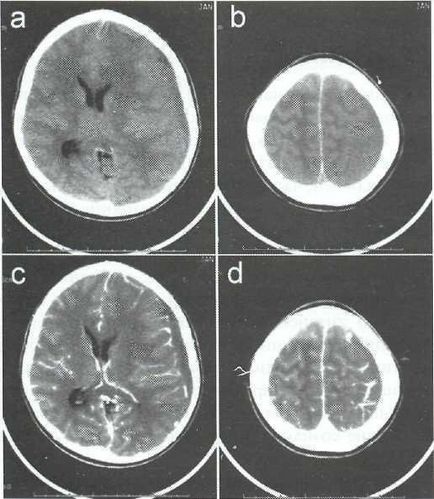

EDS diagnózist CT vagy MRI. Amikor CT EDS látható, ahol a zóna csökkentett félgömb alakú plotnos-ti (ábra. 22-1). Edges gennyes felhalmozódást egyértelműen konturiruyutsya felerősített jel beadva szemben, amely kapcsolatban van a gyulladásos folyamatok Som-kagyló. Ödéma medulla-proyav a tömeges hatása a félgömb oldalán EDS (ábra. 22-2). Szubdurális gennygyülem egyes SLE-teák kétoldalú (ábra. 22-3).

Ábra. 22-1. CT axiális szelet. Szubdurális gennygyülem: a, b - a kontraszt fokozása nélkül; a, d - a kontrasztfokozó. Az MRI a választandó módszer a diagnózis EDS, mivel lehetővé teszi, már a korai szakaszban, hogy pontosan a helyét és gyakoriságát EDS. A T1-felhalmozódás genny ad hypointense jel, és a T2 - hyperintensive, markáns agyvizenyő anyag. MRI Sí- felolvasztott legérzékenyebb módszer a diag-nosis kis empyema, amelyek nem láthatók a számítógép vizsgál.